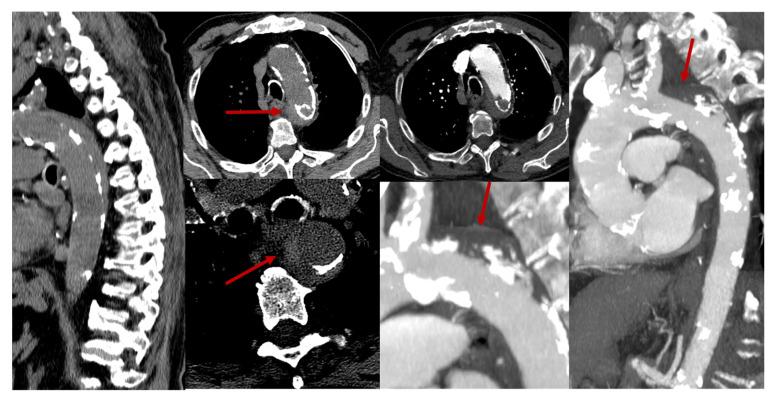

Spinal cord infarction (SCI) of arterial origin is a rare vascular event, and its incidence is probably underestimated. There are no strong epidemiological data, and the diagnostic pathway is complex and sometimes incomplete. Furthermore, many cases may be misdiagnosed as other forms of acute and subacute myelopathies. The focus of this review is the clinical and neuroradiological issues in diagnosing SCI and their respective reliability in a clinical setting. The new proposed diagnostic criteria of SCI, although not covering all aspects, highlight the need for a comprehensive approach, including even atypical cases, as the lack of cord compression on Magnetic Resonance Imaging (MRI) is the only mandatory feature for diagnosis. Some MRI features are supportive of the diagnosis, particularly when the anterior spinal artery territory is involved and diffusion-weighted imaging (DWI) is used. Several etiologies can be considered, considering traditional vascular risk factors and diseases affecting the aorta and its main branches, yet a significant proportion of cases remain without a definite etiology. The strongest predictor of SCI diagnosis is a clinical variable, i.e., a time to nadir of severe deficits < 12 h.

动脉源性脊髓梗死(SCI)是一种罕见的血管事件,其发病率可能被低估。目前尚无强有力的流行病学数据,且诊断路径复杂,有时并不完整。此外,许多病例可能被误诊为其他形式的急性和亚急性脊髓病。本综述的重点是诊断SCI的临床和神经放射学问题及其在临床环境中的各自可靠性。新提出的SCI诊断标准虽然未涵盖所有方面,但强调了采取综合方法的必要性,包括对非典型病例,因为磁共振成像(MRI)上无脊髓受压是诊断的唯一必要特征。一些MRI特征支持诊断,特别是当脊髓前动脉供血区受累并使用弥散加权成像(DWI)时。考虑到传统血管危险因素以及影响主动脉及其主要分支的疾病,可考虑多种病因,但仍有很大比例的病例病因不明。SCI诊断的最强预测因素是一个临床变量,即严重功能缺损最低点出现的时间<12小时。